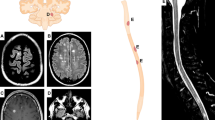

Regarding APRIL and BAFF, we found statically significant differences between the four subgroups (p = 0.003 and 0.013 respectively, ANOVA test). (Fig. 1A, B).

CSF concentration of APRIL (A), BAFF (B), CHI3L1 (C), and CCL2 (D) for each study group in pg/ml except for CHI3L1 measured as ng/ml. The boxes represent median and interquartile range. Statistical differences between groups were highlighted: a singler asteris (*) for p-value < 0.05 and double asterisks (**) for p-value < 0.01. Comparisons of CSF biomarkers concentration between multiple groups were explored with ANOVA for APRIL, BAFF, and CCL-2 and with Kruskal–Wallis for CHI3L1. Comparisons between two independent groups were assessed through Student T-test for APRIL, BAFF, and CCL-2 and with Mann–Whitney test for CHI3L1. RMS, relapsing multiple sclerosis; PMS, progressive multiple sclerosis; ONIND, other non-inflammatory neurological disorders; OIND, other inflammatory neurological disorders

RMS presented significantly lower concentrations of both APRIL and BAFF when compared to PMS (p < 0.001 and 0.024 respectively). BAFF concentrations were also lower in RMS compared to control groups reaching statistical significance only with OIND (p = 0.069 vs. ONIND and p = 0.034 vs. OIND). We did not find significant differences between RMS and control groups regarding APRIL concentrations.

BAFF concentrations did not differ significantly between PMS and both control groups. whereas APRIL concentrations were higher in PMS respect to ONIND (p = 0.037) and OIND (p = 0.096).

CHI3L1 CSF concentrations were significantly higher in both MS groups in comparison to both control groups (Fig. 1C). We did not find significant differences between RMS and PMS while CHI3L1 concentrations were significantly higher in OIND respect to ONIND (p = 0.016).

CSF CCL2 concentration was significantly lower in RMS patients respect to PMS and ONIND while PMS have comparable concentrations with both control groups. (Fig. 1D).

We did not find significant differences between groups through ANOVA test for CXCL8, CXCL10, and CXCL12 (Fig. 2A-C).

CSF concentration of CXCL8 (A), CXCL10 (B), CXCL12 (C), and CXCL13 (D) for each study group in pg/ml except for CHI3L1 measured as ng/ml. The boxes represent median and interquartile range. Statistical differences between groups were highlighted: a singler asteris (*) for p-value < 0.05 and double asterisks (**) for p-value < 0.01. Comparisons of CSF biomarkers concentration between multiple groups were explored with ANOVA for CXCL8, CXCL10, and CXCL12 and with Kruskal–Wallis for CXCL13. Comparisons between two independent groups were assessed through Student T-test for CXCL8, CXCL10, and CXCL12 with Mann–Whitney test for CXCL13. RMS, relapsing multiple sclerosis; PMS, progressive multiple sclerosis; ONIND, other non-inflammatory neurological disorders; OIND, other inflammatory neurological disorders

Despite this, we found significantly higher CSF CXCL10 levels both in RMS and PMS when compared to OIND (p = 0.038 and 0.002 for RMS and PMS, respectively).

We also found that mean CXCL8 levels were higher in MS patients compared to OIND and ONIND. These differences were statistically significant only for the PMS group.

CSF CXCL13 concentration was significantly higher in MS when compared to control groups (p < 0.001). We did not find significant differences between OIND and ONIND (Fig. 2D).